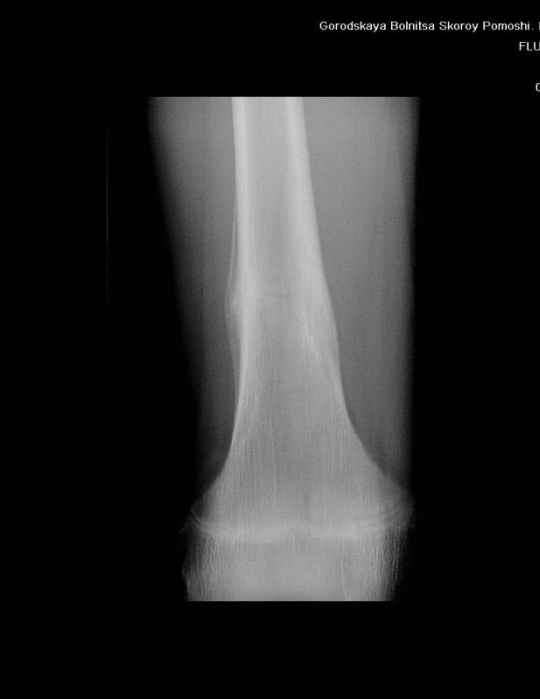

Здравствуйте, уважаемые коллеги!Представляю вашему вниманию интересный случай и пока что непонятный для меня в диагностическом плане. На днях в наше отделение (детской ортопедии и травматологии) поступил 13-летний мальчик по направлению из поликлиники с диагнозом: остеома нижней трети правого бедра.

Анамнез практически никакой: в следствие травмы (растяжение связок коленного сустава) от 07.11.2004 выполнены Rg-граммы в травмпункте и обнаружено опухолевидное образование. Первичные Rg-граммы я не публикую, так как они заметно худшего качества, да и динамики за прошедшие три недели не отражают. Болевой синдром купирован в течение трёх дней. В настоящий момент мальчика ничего не беспокоит. Ходьба не нарушена, опухоль пальпируется с трудом по задней поверхности в н\3 правого бедра, пальпация безболезненна, объем движений в суставах правой нижней конечности полный и симметричный. Кожа над опухолью не изменена.В нашей клинике проведено дополнительное обследование: общие анализы крови и мочи, биохимия крови без особенностей. Выполнены Rg-граммы на цифровом Siemens обычные и продольные томограммы срезами 3-5 мм, а также компьютерная томография поперечными срезами по 5 мм. Прошу обратить внимание, что на приведённых томограммах видны две полости 10х15 мм и 15х60 мм. Также имеются два опухолевидных образований наслаивающихся друг на друга: уплощённое и вытянутое 10х100 мм и элипсовидной формы 15х30 мм. Это хорошо заметно на фото a_1.jpg c_1.jpg и d_1.jpg. Плотность внутри полостей 125% от плотности костномозгового канала, плотность наружного опухолевидного образования 55% от плотности кортикального слоя. Также отмечается линия перелома по центру наружного опухолевидного образования.Исходя из полученных данных мнения в плане диагноза несколько разделились от 1)сочетания кортикальной фиброзной дисплазии и латентно протекавшего маршевого перелома н\3 правого бедра до 2)остеосаркомы. В отношении первого варианта не сходится отсутствие клиники при переломе такой крупной кости как бедро, второй вариант вообще оставлю без комментария, ибо некомпетентен. Хотелось бы услышать мнения коллег, с удовольствием ознакомлюсь с любыми предположениями и замечаниями.С уважением, Александр Е. КлоковОтделение детской ортопедии и травматологииБСМП г. Мурманска.